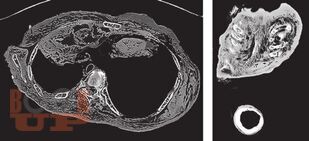

В книге рассмотрены вопросы применения методов визуализации при проведении судебно-медицинской экспертизы живых лиц и трупов. Особое внимание уделено судебно-медицинскому значению рентгенографии, посмертной компьютерной томографии и посмертной магнитно-резонансной томографии. Описаны возможности посмертной ангиографии для визуализации повреждений кровеносных сосудов. Авторы критически характеризуют преимущества и недостатки так называемой виртуальной аутопсии.